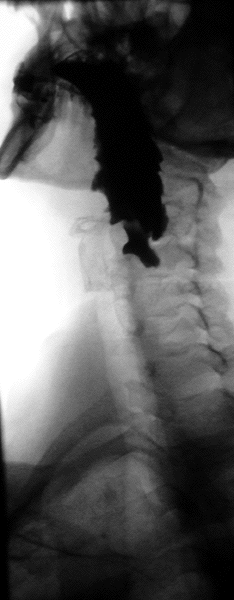

Normal barium swallow fluoroscopic image, showing the ingested barium sulfate being induced down the oesophagus by peristalsis. | |

A thick barium mixture is swallowed in supine position and fluoroscopic images of the swallowing process are made. Then several swallows of a thin barium mixture are taken and the passage is recorded by fluoroscopy and standard radiographs. The procedure is repeated several times with the examination table tilted at various angles. A total of 350–450 mL of barium is swallowed during the process.[14][15] Normally, 90% of ingested fluid should have passed into the stomach after 15 seconds.[16]